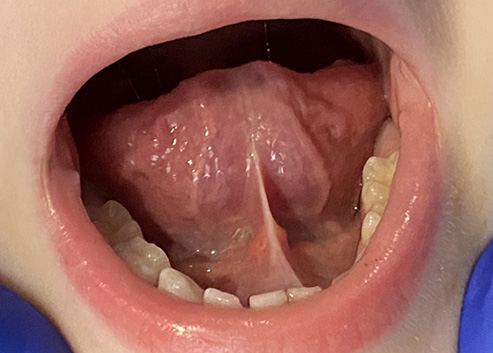

A tongue-tie (ankyloglossia) is a movement restriction of the tongue caused by an excessively tight thin tissue (frenum) connecting the tongue and the floor of the mouth. Equally, a lip-tie occurs when the tissue between the upper lip and the gums does not allow the lips to move freely, and a cheek-tie influences the movement and functioning of the cheeks.